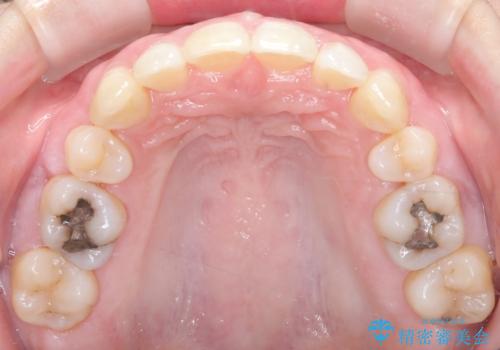

- 前歯の凸凹と前突感を改善するため、上下左右の4番を抜歯し、空いたスペースを利用して前歯を後方へ下げる審美ワイヤー矯正を計画しました。抜歯後は透明で目立ちにくい審美ブラケットを装着し、ワイヤーを用いて徐々に歯列を整えます。毎月1回の調整を通じて歯並びの変化を確認しながら、丁寧に矯正を進め、約2年で理想的な歯列と噛み合わせを完成させることを目指します。

前歯が前に出ていることや歯並びの凸凹が気になるという主訴でした。十分なスペースを確保するため上下左右の第一小臼歯(4番)を抜歯し、そこに前歯を移動させて整列を行いました。矯正装置には目立ちにくい透明なブラケットを選択し、見た目のストレスを軽減。矯正期間中は定期的な通院でワイヤーを微調整し、無理なく確実に歯を動かしました。治療後は前歯が自然な位置に下がり、口元の突出感が解消されるとともに、美しく整った口元に仕上がり、患者様にも大変喜んでいただけました。